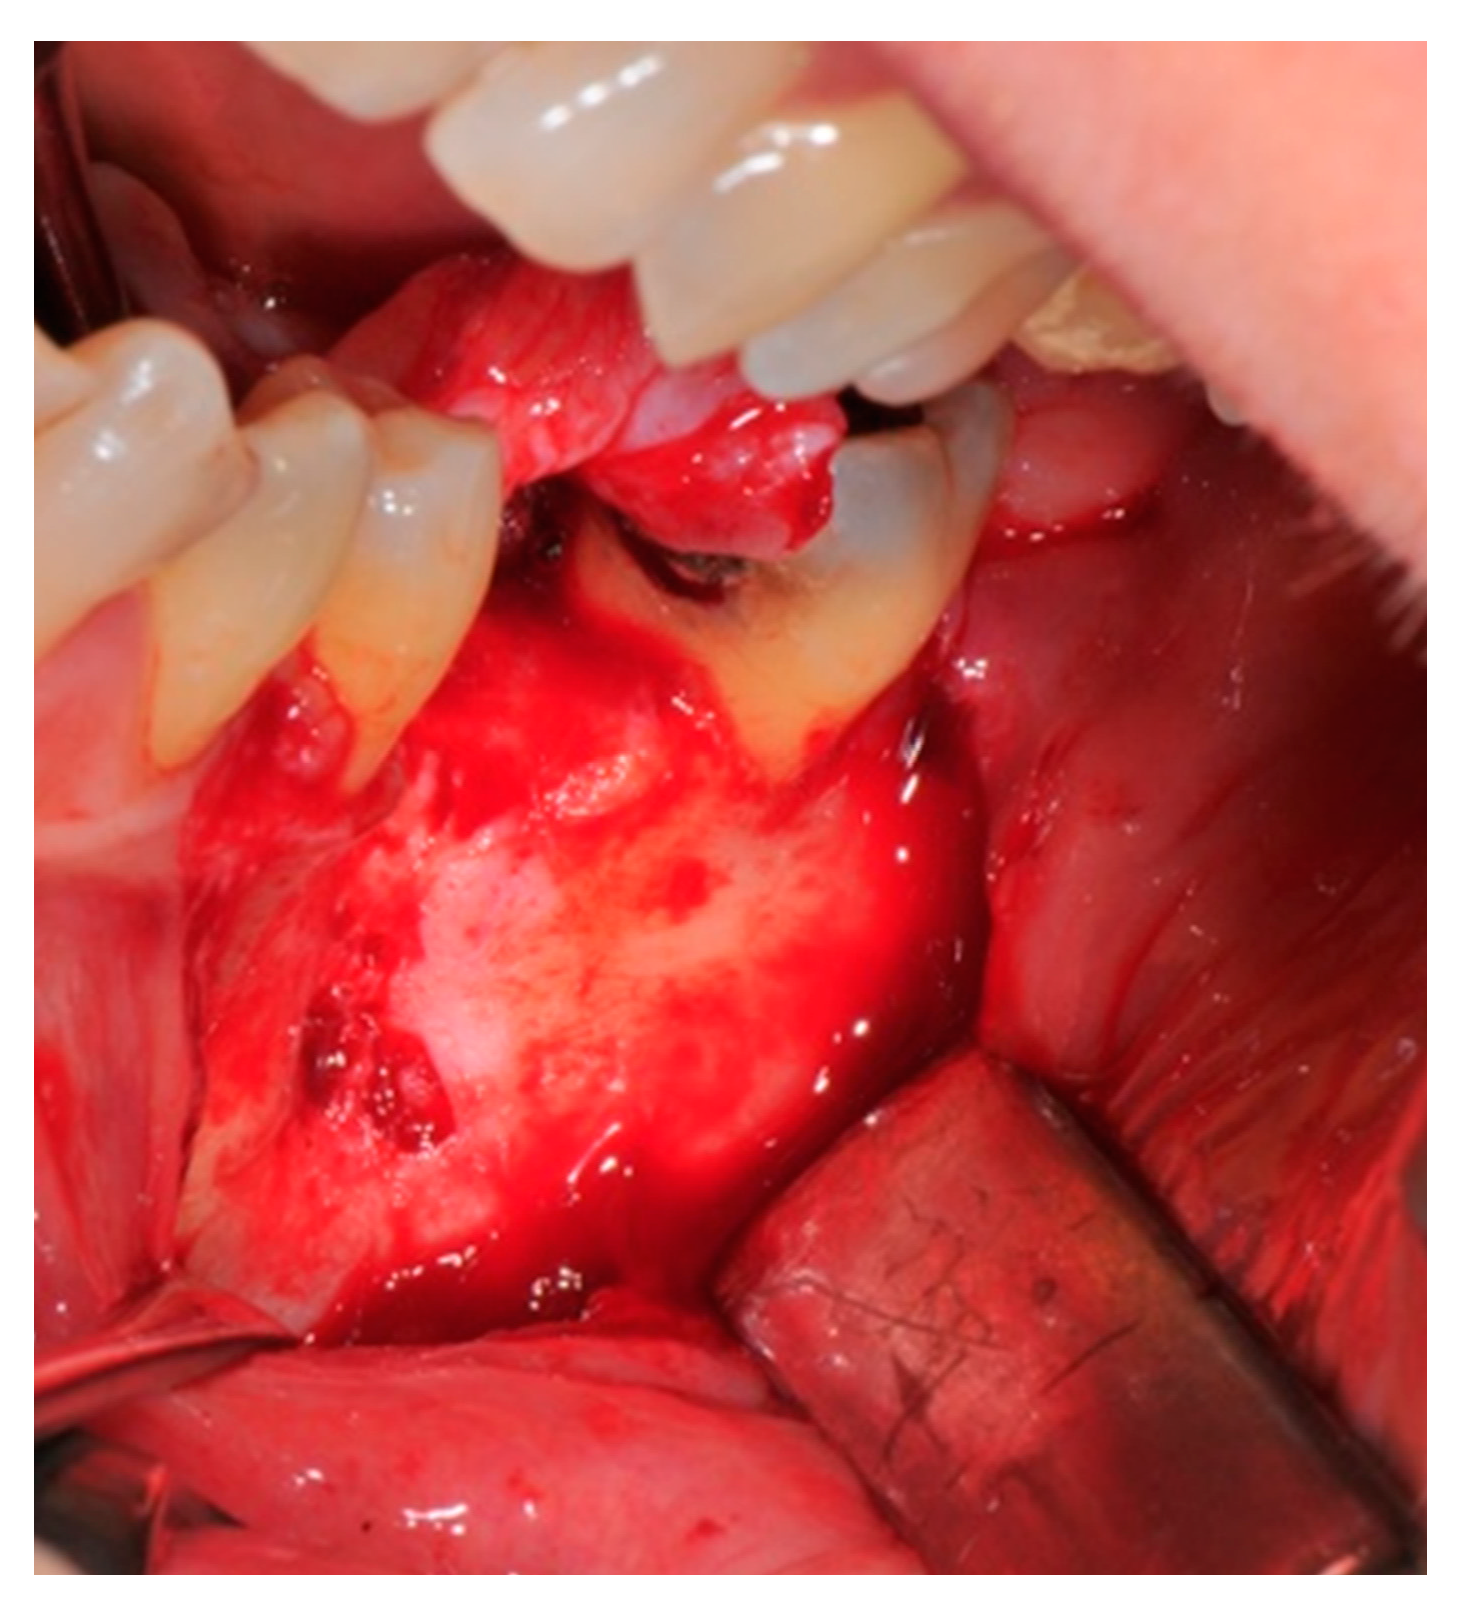

- Flap design: Soft tissue management should be as accurate as possible. The design of the flap should ensure a tension-free primary closure of the wound even after voluminous grafting of the defect. One option (preferred especially in wide vertical defects) is the execution of the so-called “poncho” flap. This technique includes a high vestibular incision of the mucosa, muscle and periosteum in order to undermine the preparation of the flap and to achieve its mobilization, followed by a deep incision in the buccal area with two additional vertical incisions that are performed at an appropriate distance from the occlusal area and the site of augmentation. After the incision, the preparation of a muco-periosteal flap and the remotion of scar tissue, a full thickness flap is raised until the bone defect is uncovered [17,18,19,20]. Finally, the positioning of the customized titanium mesh is passively tested to evaluate its fit intra-operatively (Figure 2, Figure 3, Figure 4 and Figure 5).

- Preparation of the receiving site: The exposed bone is cleaned from all of the remaining soft tissue and it is then prepared with multiple perforations using a small ball bur; this procedure is known as “bone refreshing” and it is performed to expose the cancellous portion of the residual bone, which shows a great osteo-genetic potential (Figure 6).